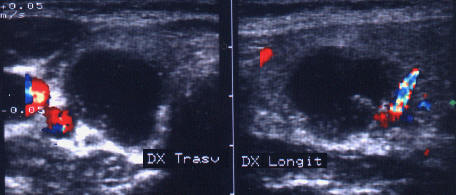

ecocolordoppler si powerdoppler- acelasi nodul

Vascularizatie interna, mai evidenta in powerdoppler.

Femeie 25 ani. Nodul unic in lobul stang, contur net, hipoecogen, respecta parenchimul din jur, neomogen, de 18x23x36 mm (7,5 cc).

Citoaspiratia cu ac subtire: nodul adenomatos.

Examen histologic postoperator: adenom trabecular fetal.

Acelasi caz. La doppler color - vascularizatie interna, mai evidenta in powerdoppler.